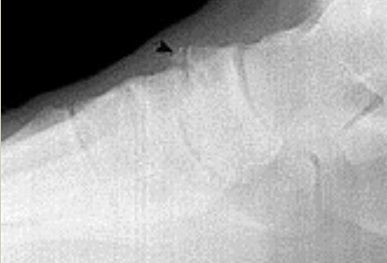

What is this? | Calcaneonavicular coalition (AKA calcaneonavicular bar or anteater's nose) |